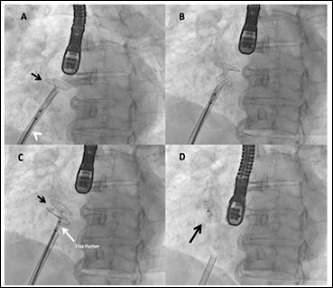

The patient gave informed consent to undergo restrictive atrial septostomy. Using real-time Transesophageal Echocardiographic (TEE) guidance, the inter-atrial septum was crossed through a patent foramen oval with a multipurpose catheter. A balloon-based atrial septostomy was performed with a 14-mm non-compliant over-thewire balloon (Figure 1), the balloon diameter being 6 mm larger than the planned fenestration diameter of the Atrial Flow Regulator (AFR) device (8 mm).

Figure 1: A) Two-dimensional color Doppler Transesophageal Echocardiography (TEE) biplanar view showing the guide wire (white arrow) crossing a patent foramen ovale; B) Dilatation of the atrial septum with a noncompliant balloon (yellow arrow); C) Fluoroscopic image of the guide wire placed into the upper left pulmonary vein; D) Inflated over-the-wire balloon (black arrow).

Note: RA: Right Atrium; LA: Left Atrium